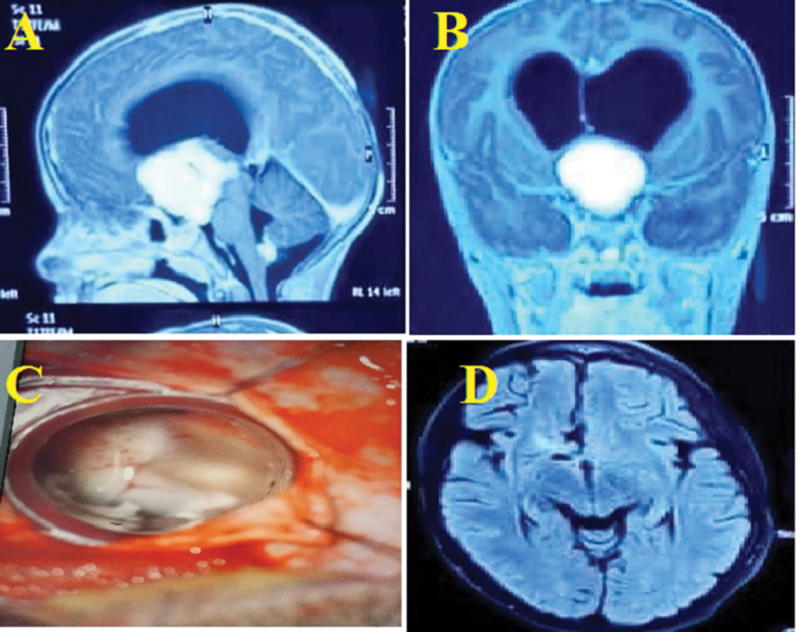

Materials and methods: We retrospectively studied 157 patients with deep-seated intracranial lesions who underwent microscopic resection with the help of a tubular retractor made of a plastic syringe and Teflon introducer between January 2018 and January 2024 in a tertiary hospital. All deep-seated lesions were such as neurocytoma, lymphoma, ependymoma, colloid cysts, metastatic brain tumors, astrocytoma, and meningiomas. We evaluated all patients postoperatively with computed tomography (CT) scan on the first/second day of surgery. The amount of blood loss, the complications, and the mortality rate were recorded.

Results: There were 104 males and 53 females with a mean age of 54.13 (range: 15-80) years. Gross total resection was obtained in 85.35% and subtotal in 14.65% of patients. Complications such as surgical bed hematoma in 5.73%, seizure in 3.18%, weakness in 2.54%, and contusion in 3.82% of patients were noted. The blood loss varied from 30 to 500 mL (average, 100 mL). The mortality rate was observed in 2.54% of all patients. Follow-up ranged from 1 to 25 months (average, 10 months).

Conclusion: Plastic syringe tubular retractor with Teflon introducer system is safe and effective for the treatment of deeply located intracranial lesions in terms of low morbidity and excellent rate of resection.